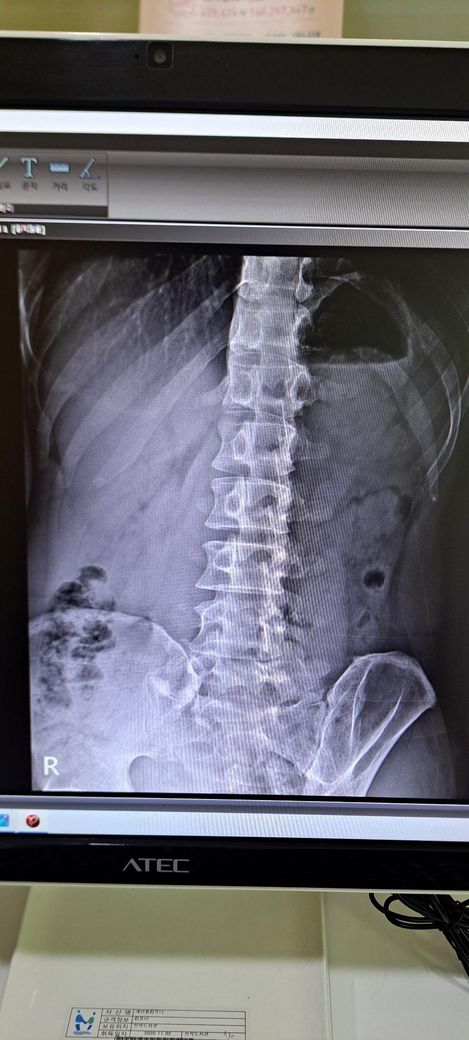

x ray 촬영한 영상인데 골반 틀어짐 및 전방경사 심각한가요? 골반 틀어짐은 어느 쪽을 교정해야 하며 골반 틀어짐 및 전방경사 교정 방법을 알려주시면 감사하겠습니다 .

사진상으로 골반 좌우 비대칭은 약간 의심되지만, 단순 X-ray만으로 "심각한 틀어짐"이라 단정하긴 어렵습니다.

일단 골반 같은 경우 좌우 대칭이 다르며 약간의 전방 경사 및 틀어짐이 있는 것으로 보입니다.

정면 사진상 골반의 좌우높이 차이가 관찰되며, 이는 대퇴골의 위치변화와 연관되어 보입니다. 측면 사진에서 요추의 곡선이 다소 꺾여 있는 양상이 보여 골반 전방경사 가능성이 큽니다. 정면 영상에서 척추가 일직선이 아니라 완만한 S자 형태로 휘어있는 측만 소견이 보입니다. 심각한 수준은 아니나 지속적인 관리가 필요한 상태입니다. 측면 사진상 경추의 커브를 보면 일자목 상태입니다. 골반이 높은쪽의 근육은 이완시키고, 낮은쪽과 약해진 둔근, 복근을 강화하는 운동이 필요합니다. 전방경사 완화를 위해 장요근 스트레칭과 프랭크 같은 코어 운동이 효과적입니다. 흉쇄유돌근 스트레칭과 더불어 등 근육을 강화하여 어깨를 펴는것이 급선무입니다.

골반 틀어짐을 보면 오른쪽 골바 날개가 왼쪽보다 높이 위치한걸 볼 수 있습니다. 하지만 이 사진만으로 판단하기보다는 발끝까지 찍은 사진을 보고 왜 오른쪽 골반이 더 위로 높아져있는지를 판단해야 원인과 해결법을 판단할 수 있겠습니다.

척추측만은 의미있는 정도가 아닙니다. 저희가 20도 이상을 증상을 유발할 수 있는 측만으로 보는데 그만큼 측만이 확인되지 않습니다.